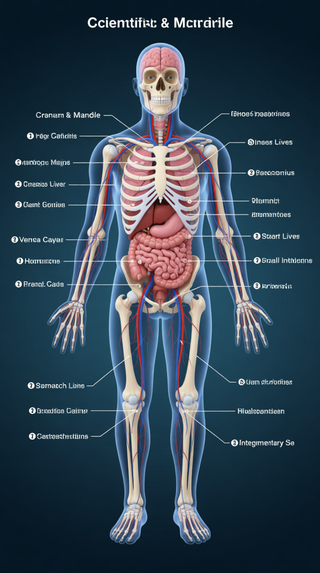

Creates ultra-detailed, multi-layer 3D anatomical visualizations from reference photos.Open

Creates ultra-detailed, multi-layer 3D anatomical visualizations from reference photos.Open

Transform photos into scientific anatomical illustrations.Open

Transform photos into scientific anatomical illustrations.Open